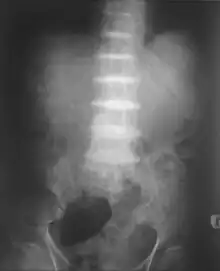

Intervertebral discs calcification due to ochronosis

After the age of 30, people begin to develop pain in the weight-bearing joints of the spine, hips, and knees. The pain can be severe to the point that interferes with activities of daily living and may affect the ability to work. Joint-replacement surgery (hip and shoulder) is often necessary at a relatively young age.[1] In the longer term, the involvement of the spinal joints leads to reduced movement of the rib cage and can affect breathing.[1] Bone mineral density may be affected, increasing the risk of bone fractures, and rupture of tendons and muscles may occur.[1]